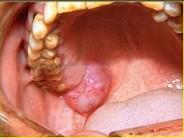

以下关于黏液表皮样癌(如图)的叙述中,哪项是错误的 ( )

A高分化黏液表皮样癌很少发生颈淋巴结转移

B女性多于男性,发生于腮腺者居多

C低分化黏液表皮样癌淋巴结转移率高

D高分化和低分化者均应作选择性颈清

E高分化黏液表皮样癌较低分化黏液表皮样癌常见